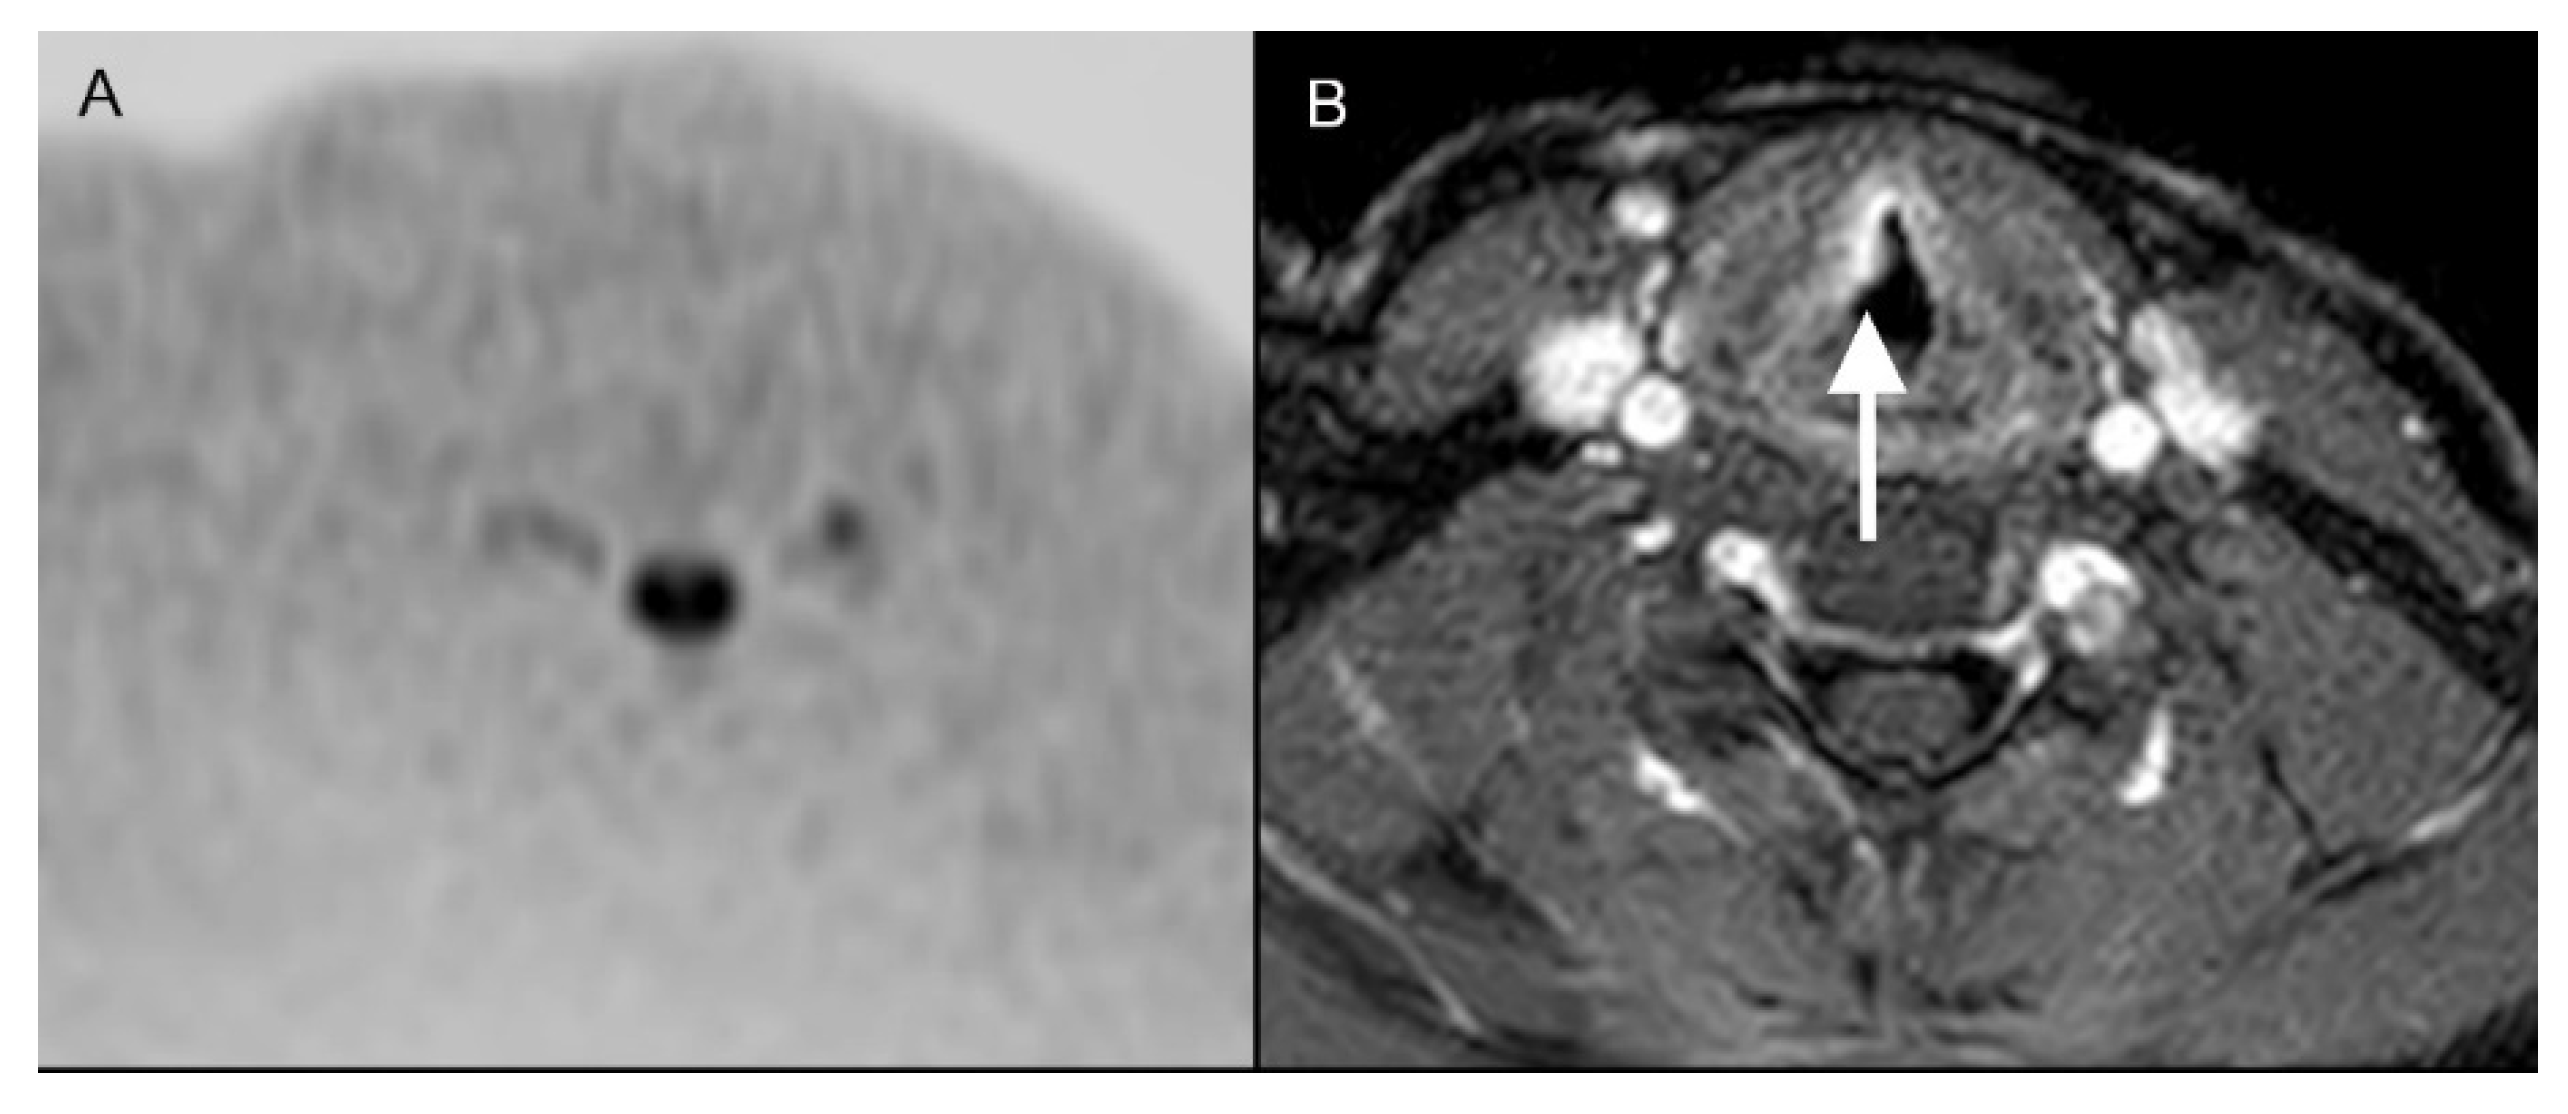

3.2. Findings of Standard MRI

3.3. Findings of DWIBS

3.4. Findings of Standard MRI + DWIBS